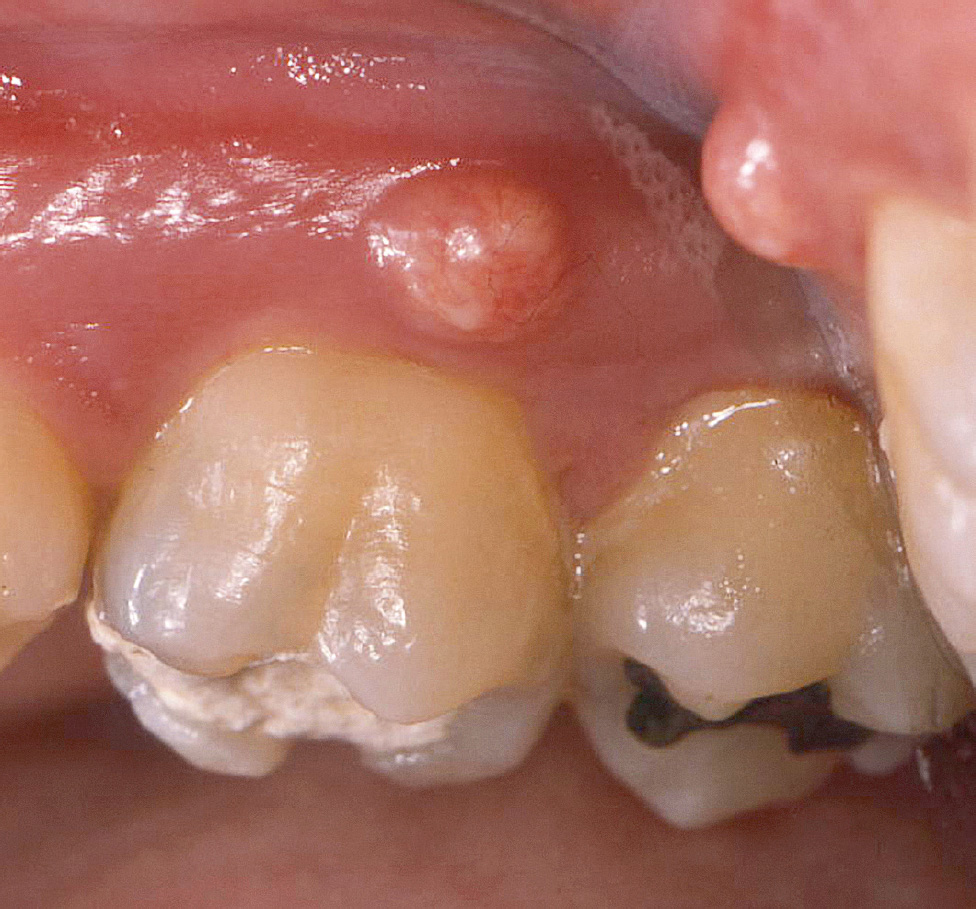

Parodontalabszesse (Abb. 5, Tab. 10) und Endo-Paro-Läsionen gehören neben den nekrotisierenden Parodontalerkrankungen zu den wenigen Parodontalerkrankungen, die Schmerzen verursachen. Beide Arten von Läsionen gehen mit sehr rascher Gewebezerstörung einher und erfordern deshalb unmittelbares therapeutisches Handeln. Neben Schmerzen werden als Symptome häufig Empfindlichkeit der Gingiva, Schwellung und Anhebung des Zahnes berichtet. Parodontalabszesse können bei Patienten mit unbehandelter Parodontitis oder nach Therapie, aber auch bei Patienten, die keine Parodontitis haben, auftreten (s. Tab. 10)5.

Abb. 5 Parodontalabszess, ausgehend von einer durchgängigen Furkation an Zahn 16.